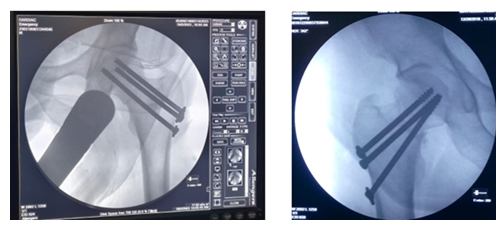

The screw lengths are measured, and drilling is performed using a 4.5 mm cannulated reamer. The screws are then inserted (for the BDSF technique, a specific sequence of middle, then superior, and lastly inferior screw insertion is to be followed). All three screws are inserted less than 5 mm subchondrally (Figure 3,4). In all cases, a prophylactic antibiotic was given. In the postoperative ward, proper fluid and hemodynamic balance were ensured. Change of posture was done twice an hour. The antibiotic was continued for 3 days. Analgesics were given to ensure a pain-free postoperative period. On the first postoperative day, patients were allowed to sit on the side of the bed. Patients were being educated about breathing exercises, isometric quadriceps exercises, gluteal exercises, and ankle pumping exercises. An immediate postoperative X-ray was done (Figure 5). After checking the dressing, on 4th POD, they were discharged from the hospital if their postoperative period was uneventful. Oral antibiotics were given for 10 days. Advice was given to continue isometric quadriceps exercise. Regarding ambulation, they were advised to do non-weight-bearing (of the affected side) crutch ambulation until directed by the physician. Use of elevated toilet seats onwards is also advised. The next follow-up would be given at the 14th POD. The first follow-up was given at 14th POD to check any signs of infection, pain status, and distal neurovascular status. The stitch was removed on the same day. Advice given about isometric quadriceps exercise, active abduction, extension exercise, and stretching exercise of the hip joint. The next follow-up was the 6th week after the operation. The range of motion was tested. An X-ray was done to check callus formation. Improvements were noted. Partial weight bearing was given at this follow-up. Subsequent follow-up was given at 12 weeks and every 4 weeks until union has been achieved or at least 9 months (Figures 6-10).